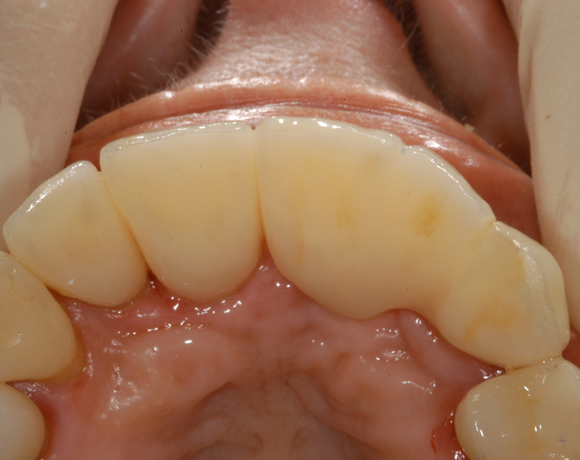

Bei dieser Patientin waren die Zähne 16, 12, 11 und 21 mit einer Modellgußprothese versorgt.

Der Zahn 13 war aus parodontalen Gründen stark gelockert und sollte extrahiert werden.

Als Ersatz wurden drei Implantate für die Zähne 13, 11, 21 gesetzt, die Lücke 15 – 17 mit einer

vollkeramischen Brücke versorgt. da die Patientin eine metallfreie Versorgung wünschte,

wurden Zeramex C Implantate gewählt, auch der Zahn 22 wurde mit einer vollkeramischen

Krone versorgt.